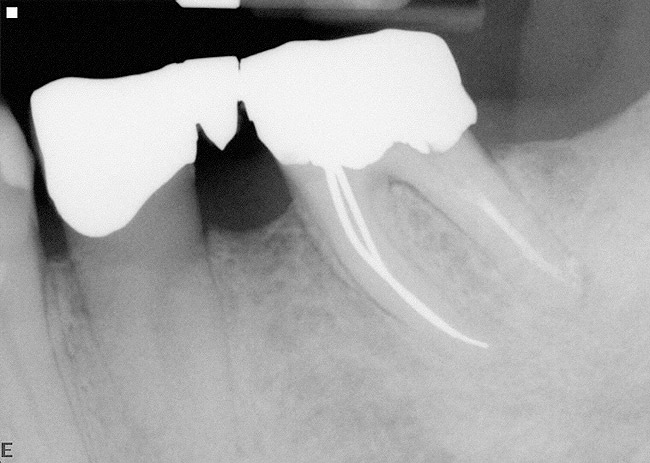

3. Extraction of a hopeless mandibular molar, defect debridement, and placement of an implant in one of the root sockets, followed by restoration with a molar-sized crown. This approach addresses the concern of two implants being placed closely together in the root extraction sockets. However, this treatment appropriately results in a mesial cantilever of the implant restoration and an area of potential plaque accumulation (Figure 1).

Figure 1  An implant has been placed in the mesial root socket at the time of mandibular molar extraction. The subsequent restoration demonstrates a significant cantilever and is not conducive to effective home care efforts.

Figure 1